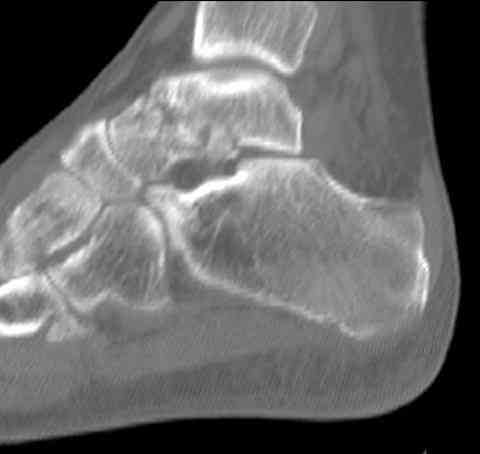

И второй случай из недавней ташкентской практики, (извините за качество ренгенограммы и только в одной проекции) случай падения с высоты (кстати моего друга - известного киноактера) - открытый

смещенный перелом тарана, с переломом переднего края дистального эпиметафиза большеберцовой кости.

При поступлении в приемной сделана первичная обработка с ушиванием открытой латеральной раны и вытяжением за пятку.

Из-за отсутствия времени пришлось оперировать на второе утро, из материала, что имеем на месте, фиксирован двумя шурупами, а третий-это контур сломанного жойстика в 4 мм. На дистальный медиальный конец тибиа antiglide 3.5 мм пластина. Через пару дней выписан и несмотря на предупреждение, самостоятельно начал нагрузку в 4 недели, время не ждет, снимается в боевике в Росийской Федерации.